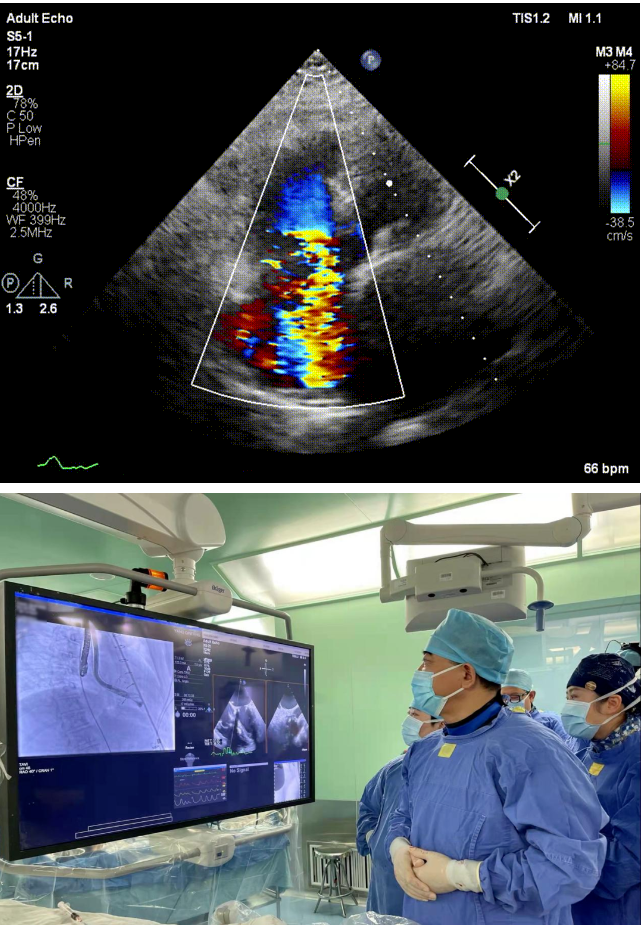

本次接受治療的患者是一名74歲的女性,14年前因風濕性心臟病行二尖瓣生物瓣植入術(shù),合并房顫。近3年來反復因腹脹、納差、下肢水腫入院,藥物治療欠佳。心臟超聲顯示三尖瓣極重度反流(有效反流口面積:0.76cm²,反流容積:79ml),繼發(fā)性右房室增大及上、下腔靜脈增寬(右房上下徑*左右徑:52*41mm,右室左右徑:46mm,下腔靜脈:29mm),右室收縮功能正常,肺動脈收縮壓 43mmHg,左心室射血分數(shù)73% ?;颊呒韧_胸手術(shù)史,術(shù)前評估STS 評分為7.02分,CRS 9分,無法接受體外循環(huán)下三尖瓣外科手術(shù)。面對這一傳統(tǒng)治療無法解決的困境,葛均波院士及其團隊周達新教授、潘文志教授、張源博士、陳莎莎博士及心超室的潘翠珍教授、李偉教授經(jīng)過討論決定,采用創(chuàng)新的Lux-Valve Plus系統(tǒng)為患者進行經(jīng)血管三尖瓣置換。

手術(shù)在患者全麻狀態(tài)下進行,采用經(jīng)右側(cè)頸靜脈作為入路,將裝載有人工瓣膜的輸送器緩慢推送至右心房;并在經(jīng)食道超聲和DSA的引導下小心調(diào)整輸送器角度,將輸送器送入右心室;逐步釋放瓣膜錨定裝置和盤片,調(diào)整瓣膜位置后,錨定瓣膜完成植入。術(shù)后右房壓明顯下降,從術(shù)前的25/10(16) mmHg降至術(shù)后即刻的12/7(10) mmHg,術(shù)后超聲提示人工三尖瓣同軸性良好,固定牢固,無反流及瓣周漏,手術(shù)室即刻拔除氣管插管。